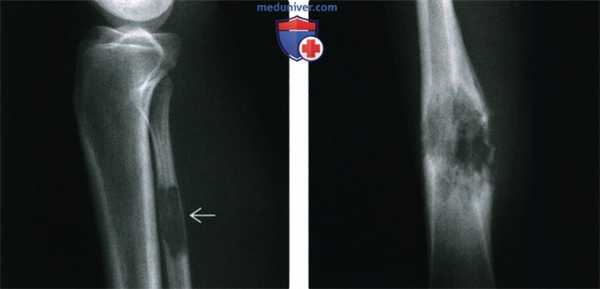

(Справа) Рентгенография вторичной ЗФГ в ПЗ проекции: типичные признаки инфаркта в проксимальном отделе большеберцовой кости, однако выраженные литические изменения очага визуализируются дистальнее. Это указывает на агрессивный характер очага. (Слева) Рентгенография в боковой проекции, другой пациент: в проксимальном отделе большеберцовой кот отмечаются признаки кальцификации, типичные для инфаркта кости. Структура очага в дистальной части меняется, приобретая литический характер с широкой переходной зоной, что указывает на вторичную ЗФГ.

(Справа) Рентгенография в ПЗ проекции: литический, деструктивный очаг с прорывом медиального кортикального слоя и значительным мягкотканным компонентом. Локализация и вид очага у пациента в этом возрасте наиболее типичны для остеосаркомы. Тем не менее, по результатам биопсии была диагностирована вторичная ЗФГ, развившаяся на фоне инфаркта кости.